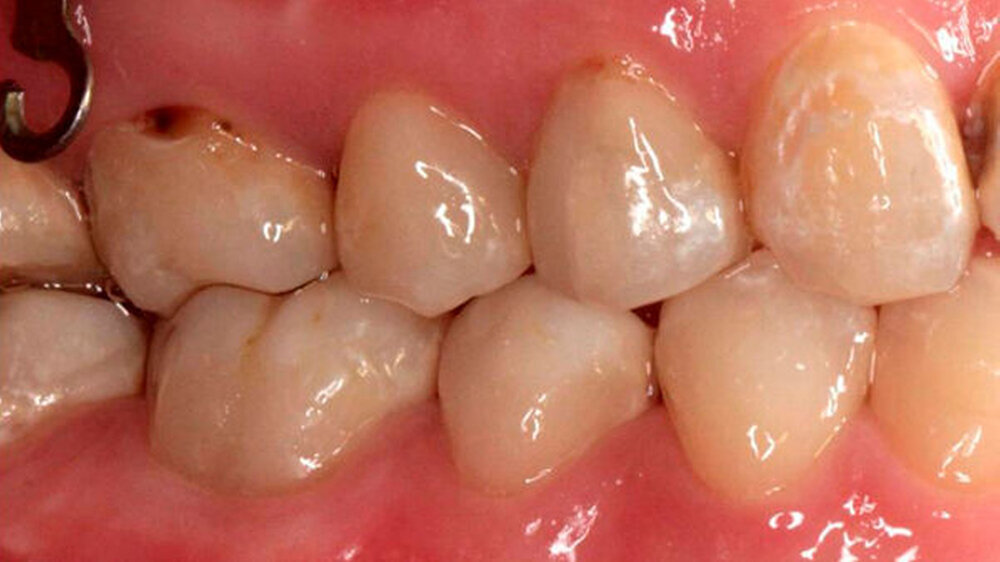

Die Kieferorthopädische Klinik (National Taiwan University Hospital) überwies die 18-jährige Patientin zur Behandlung von Karies und Wiederherstellung der Okklusion. Es wurde festgestellt, dass viele ihrer Zähne große alte Füllungen und Sekundärkaries aufwiesen.

Das Röntgenbild zeigte, dass die Füllungen bei Zahn 45 und 46 nahe an der Pulpakammer lagen. Mit EPT (32/80, 35/80) und thermischen Tests wurde die Pulpavitalität geprüft (normal). Die Diagnose lautete: tiefe Karies. Die Kompositfüllungen wurden daraufhin möglichst substanzschonend ersetzt.

Die Behandlung umfasste zwei Termine (erster: Zahn 46 und 45, zweiter: Zahn 43 und 44). Zur Entfernung der alten Füllungen dienten ein runder und ein zylindrischer Diamantbohrer sowie langsam laufende Hartmetallbohrer und zur Feinbearbeitung der Kavitäten ein Ultraschallinstrument. Nach selektiver Schmelzätzung applizierte man das Adhäsiv XP BOND®. Das Dentin wurde durch SDR ® ersetzt. Dann wurden mit ceram.x one® d3 und e2 jeweils der Rest der Kavität und die Höcker restauriert. Finiert und poliert wurde mit dem Soflex Poliersystem.

Die Restaurationen erfolgten minimal-invasiv. Durch Wiederherstellung der natürlichen Morphologie wurde für eine stabile Okklusion gesorgt. Auch bei der Kontrolle nach 9 Monaten machten die Füllungen morphologisch und farblich einen guten Eindruck. Ästhetik und Funktion gingen Hand in Hand.